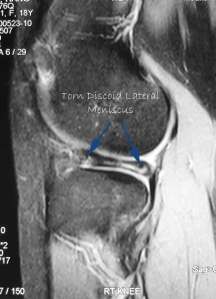

The diagnosis is made with clinical history and examination. Usually an MRI scan is necessary to clinch the diagnosis.

This is my patient who is 18-years-old and she presented with acute locking and pain in the right knee. MRI confirmed a torn discoid lateral meniscus.